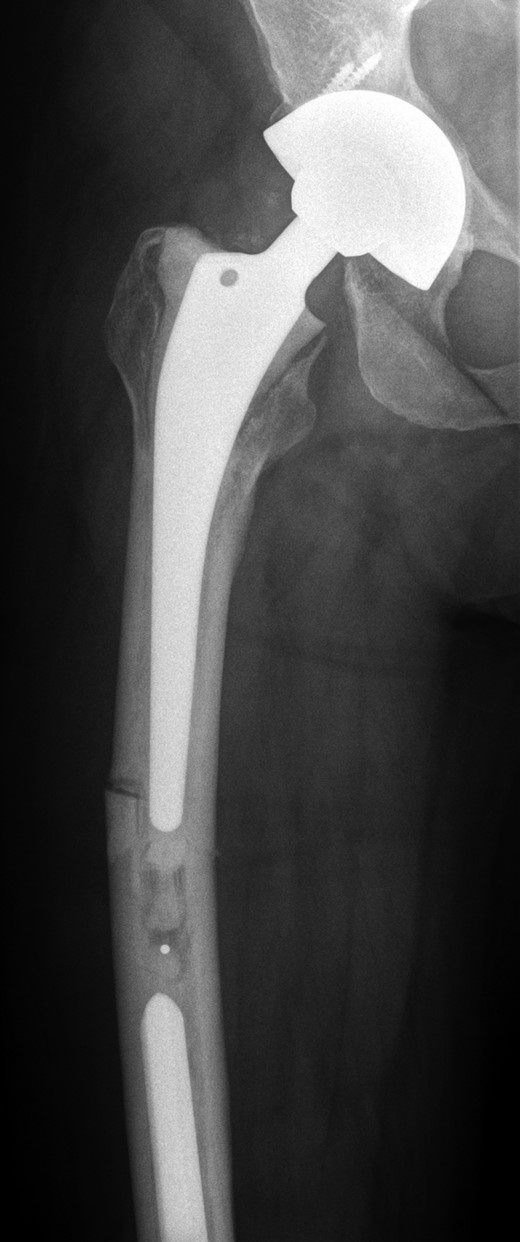

She subsequently sustained a periprosthetic fracture at the distal tip of her right total hip replacement (Fig. 1). An initial attempt was made to manage this fracture with a plate and Dall-Miles cables (Fig. 2); however, the fracture did not unite. The patient went on to have a custom-made cement-linked internal proximal femoral replacement, which had a hollow cylindrical design to accept the stem of the existing well-fixed distal femoral component (Figs 3 and 4). This linked prosthesis effectively converted her separate prostheses to a total femoral replacement, sparing her distal femoral replacement from revision. She had no problems postoperatively and recovered well from her surgery.

Custom-made cement-linked internal proximal femoral replacement.

Existing distal femoral replacement with stem linked to custom-made internal proximal femoral component visible in upper half of the image.